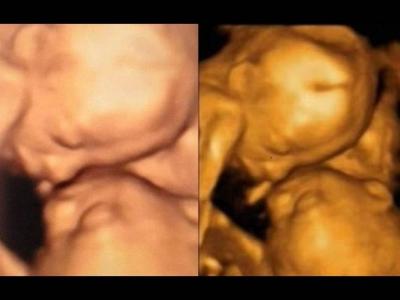

美国食品及药物管理局(FDA)警告拍3D超

FDA指,超声波测试应只用作医学用途,及由执业医护人员负责。 (蜘蛛网报道)美...